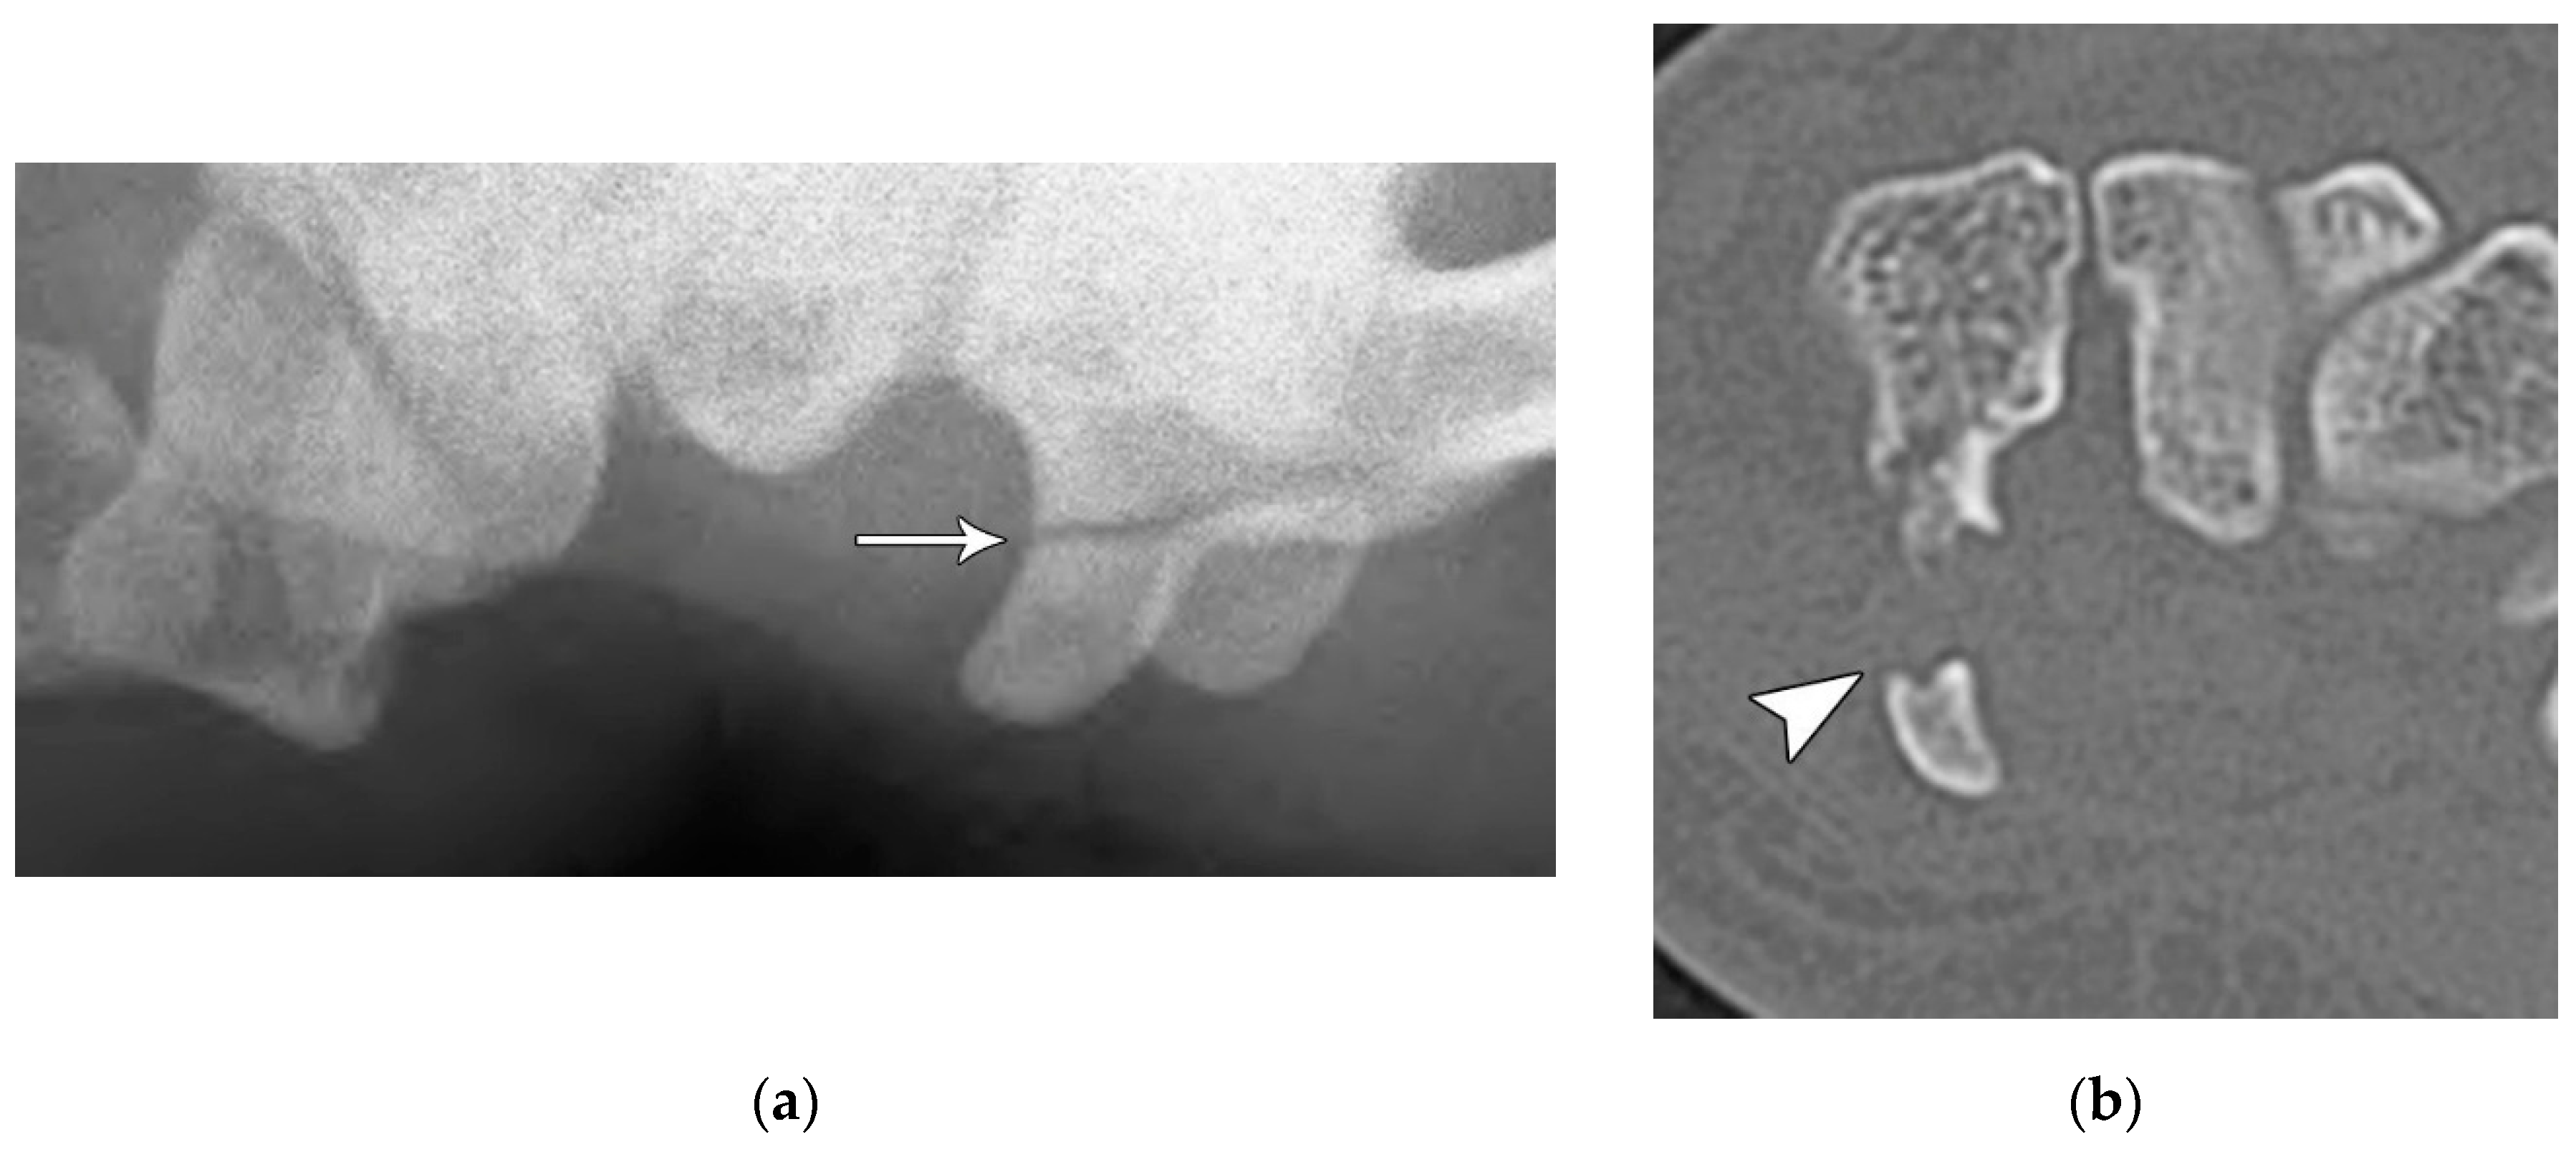

Figure 14. (a) Tunnel view hand radiograph showing a fracture through the waist of the hook of the hamate (arrow). (b) Axial CT images showing a highly displaced, comminuted fracture of the hook of the hamate (arrowhead).

Like the trapezium, hamate fractures are subdivided into body and hook fractures. Body fractures occur with a variety of fracture patterns without any specific difference in management related to the fracture types [20]. For non-displaced hamate body fractures, treatment with 4 to 6 weeks of cast immobilization is adequate while displaced hamate body fractures require open reduction and internal fixation to prevent hamatometacarpal subluxation and limited functional recovery. Hook fractures are usually caused by a direct impact trauma, or from sports where a handle is held, resulting in avulsion fractures at the pisohamate ligament attachment (Figure 14A). Tenuous blood supply to the hook (50%) results in nonunion with waist and tip fractures. Ulnar nerve paresthesia or hand weakness may also possibly occur if the ulnar nerve is injured as it passes around the hook of hamate (Figure 14B). Management of hook fractures necessitates prompt diagnosis to prevent a variety of complications if treatment is delayed. These include symptomatic nonunion, ulnar neuritis, hypothenar hammer syndrome, and flexor digitorum profundus tendon rupture. With casting for nondisplaced fractures, patients should be counseled about the prolonged immobilization required due to poor healing rate, as well as the potential complication of nonunion. For displaced or chronic fractures, as well as those with ulnar nerve compression, excision of the hook is preferred to open reduction/internal fixation because studies have shown that there is no increased restriction in wrist range of motion or grip strength with hook excision [17].